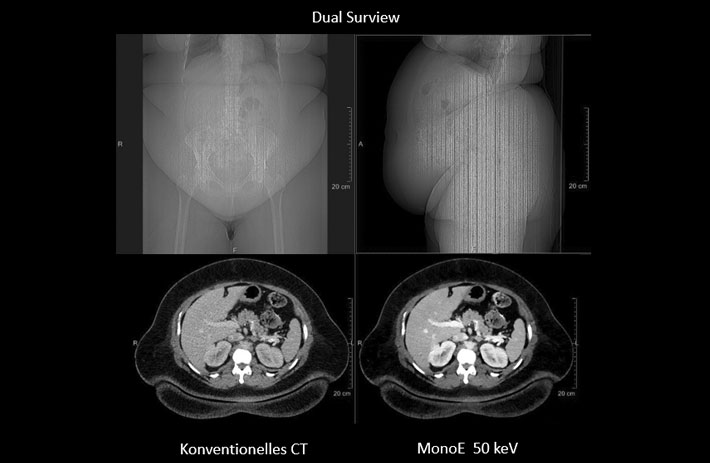

Mit dem Spektral-Detektor-CT werden Spektraldaten automatisch bei jedem Scan erfasst. Die Informationen stehen jederzeit auf der Scankonsole, der CT-Workstation sowie an jedem PACS-Arbeitsplatz zur Verfügung, sodass es nicht notwendig ist, den Patienten erneut zu scannen, bspw. wenn initial zufällige Anomalien festgestellt wurden. Dadurch profitieren Anwender durch eine höhere Diagnosesicherheit und weniger Nachuntersuchungen auf anderen bildgebenden Systemen. Unsere Fallsammlung zeigt, welchen klinischen Mehrwert der Spektral-Detektor-CT in unterschiedlichsten Anwendungsbereichen in der klinischen Routine bringt. Jede Woche gehen neue Fälle live.